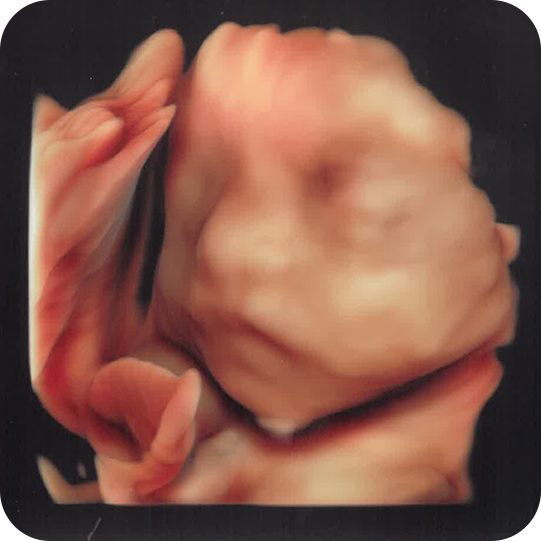

4Dエコー外来では、国内最高峰の最新機種で、赤ちゃんの顔の表情や動きをリアルタイムで確認できます。

タイミングが合えば、あくびや指しゃぶり、笑う瞬間が見れるかもしれません。

25週

26週

27週

32週